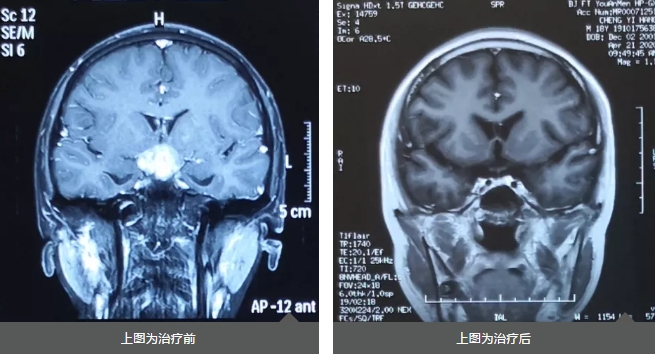

2019年8月26日,头部核磁检查结果:鞍上及三脑室占位,大小约2cm。三脑室及鞍上池占位,考虑生殖细胞瘤伴双侧脑室、三脑室、透明隔区多发种植播散。通过穿刺活检,进一步确定就是颅内生殖细胞瘤。

2019年12月03日,成程的放疗计划已完善,处方剂量为:全脑全脊髓Dt:2340cGy/180cGy/1f;病灶局部缩野Dt:2160cGy/12f,180cGy/1f。2020年2月6日,成程已完成所有放疗计划,恶心、呕吐症状完全消失。

2020年2月10日,复查头颅增强磁共振一切正常。